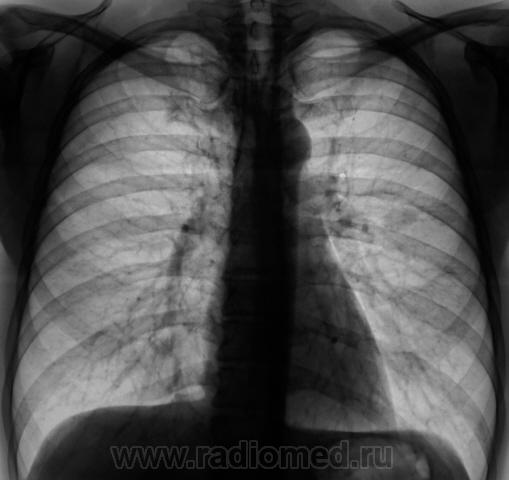

Мы долго колебались между диагнозами периферического рака и туберкуломы, остановились на "периферическом", пациент был направлен в областную онкологическую "контору", где и был прооперирован.

Слева в S6 (если не ошибаюсь) похоже на перифирический. На боковой накладывается кальцинат в л/у корня.

Если диагноз туберкулёмы слева подтвердят, то тень в S5 справа следует отнести к туберкулёме. С уважением Nikolas

Мы, благодаря "Сиару" увеличили и обработали эту тенюху, и вот что получили.

Вы оказались правы уважаемый коллега. На операции, с последующей верификацией оказалась туберкулома.